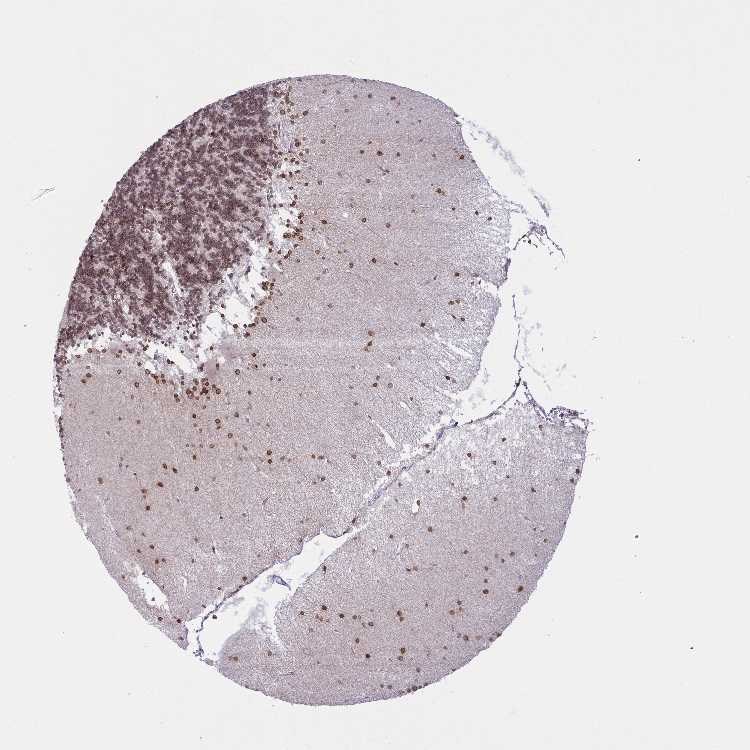

CEREBELLUM - Antibody stainingi

Antibody staining in the annotated cell types in the current human tissue is reported as not detected, low, medium, or high, based on conventional immunohistochemistry profiling in selected tissues. This score is based on the combination of the staining intensity and fraction of stained cells.

Each image is clickable and will lead to virtual microscopy that enables deeper exploration of all samples and also displays staining intensity scores, fraction scores and subcellular localization as well as patient and tissue information for each sample.

Antibody HPA018437Antibody HPA023960Antibody HPA049497Antibody HPA051675Antibody CAB034063

Purkinje cells MediumHighLowNot detectedNot detected

Cells in granular layer Not detectedMediumMediumLowMedium

Cells in molecular layer LowMediumLowNot detectedHigh